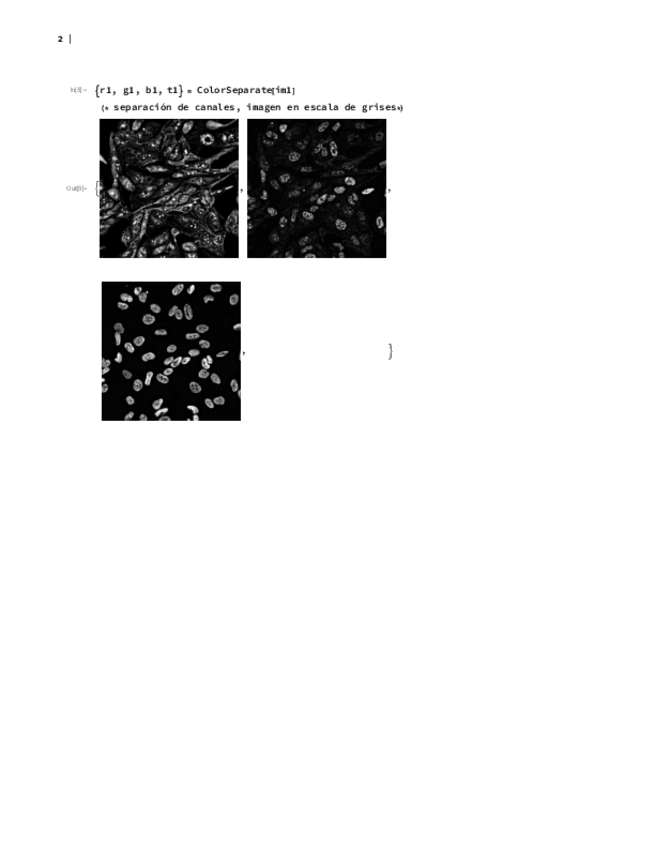

He publicado nuevos ejercicios de 3º Técnicas Instrumentales Avanzadas: ENTREGA-FINAL-WOLFRAM.pdf

25 páginas